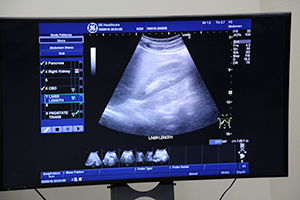

小川氏による腹部超音波のハンズオンセミナー

セミナーでは2名の演者が登壇し,講演に続き,それぞれハンズオンセミナーを行った。1題目に,日本大学病院消化器内科科長/超音波診断センター長の小川眞広氏が,「かかりつけ医のための腹部超音波手技の実際」をテーマに講演した。小川氏は,超音波検査は客観性の低さなどからマイナーな検査法として位置づけられているのが現状であるが,診断装置の中で最も分解能の高い検査ができるモダリティであると述べ,症例を示しながら超音波検査の実力を説明。超音波検査を用いることで診断への確実なショートカットができるとして,触診感覚で超音波診断装置を活用する有用性を強調した。また,弱点である客観性を改善するために,同院ではスクリーニング検査撮影法の統一化を行い,ダブルチェックができる環境も構築していることを紹介し,レポート記載の均質化の重要性についても説明した。そしてハンズオンでは,腹部スクリーニング検査における撮影テクニックについて,実演しながら詳細に説明した。

ハンズオンセミナーでは,リアルタイム超音波画像とともにプローブを操作する手元映像もWeb配信され,視聴者にとって実践的な内容となった。 |